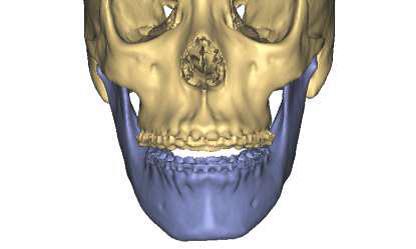

Prediction and Preoperative Workup with Model Surgery

The surgical team spends much time and energy in collaboration with the orthodontist to plan the surgery.  A joint treatment plan is devised.  The orthodontist sets up for the surgery with braces.  The surgical team then plans the surgery using xrays to predict the movements, performs the surgery on models, then fabricates acrylic splints to guide the surgical team in the operating room.